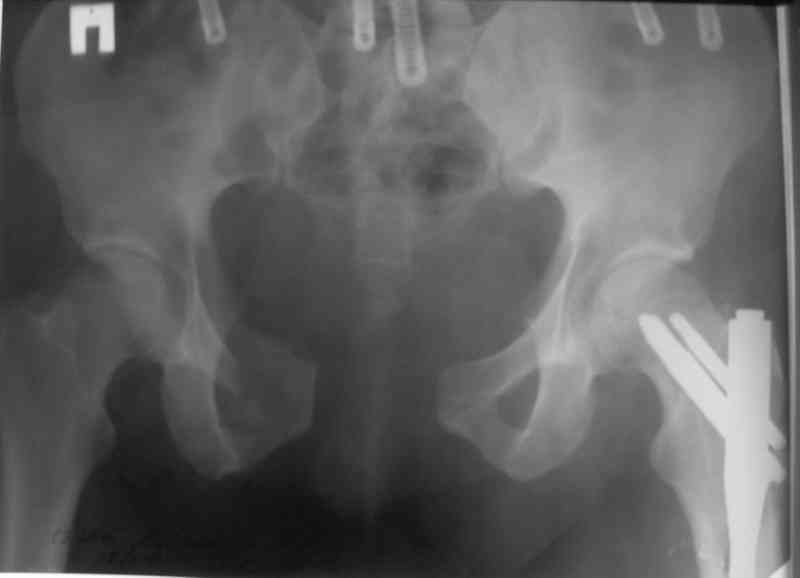

> По техническим причинам стабилизация переломов в день травмы не была выполнена. До сегодняшнего дня

> находился на вытяжении.

Можно конечно и сразу все, особенно если таз окончательно собираетесь фиксировать аппаратом. Но это тяжело для персонала и не очень нужно больному. По лодыжку нужно думать в последнюю очередь. Больше всего неприятностей больному доставляет перелом бедра. У нас были такие пациенты и мы делали в первую очередь

перелом бедер. Одной девушке, удачно приземлившейся с 11-го этажа, в один наркоз заштифтовали два бедра и наложили аппарат на таз окончательно, пятками и лодыжками занимались намного позже. В другом случае у 160-кг

пациента с вторично заживающей раной после лапаротомии забили гвоздь и только через три недели (после заживления лапаратомной раны) фиксировали переднее полукольцо пластинами. Это тучный пациент лечение в аппарате не перенес бы.

> метод фиксации таза: стержневой аппарат (тазового набора Илизарова нет в округе)

> каннюлированными винтами,

> передняя фиксация пластиной правого крестцово- подвздошного сочленения

Пластина спереди (на лонные кости) открыто и каннюлированные винты с обеих сторон сзади - закрыто.

Предварительная репозиция может быть достигнута при помощи аппарата.